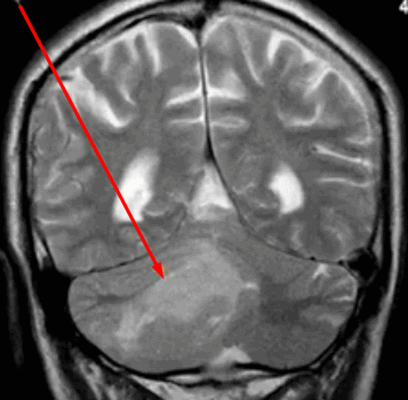

Эпендимома при МР-сканировании головного мозга

- эпендимомы — предположительно образуются в эмбриональном периоде. Характеризуются четкими контурами, плотнее, чем здоровые ткани, редко вызывают отек, чаще обнаруживаются в полостях желудочков;